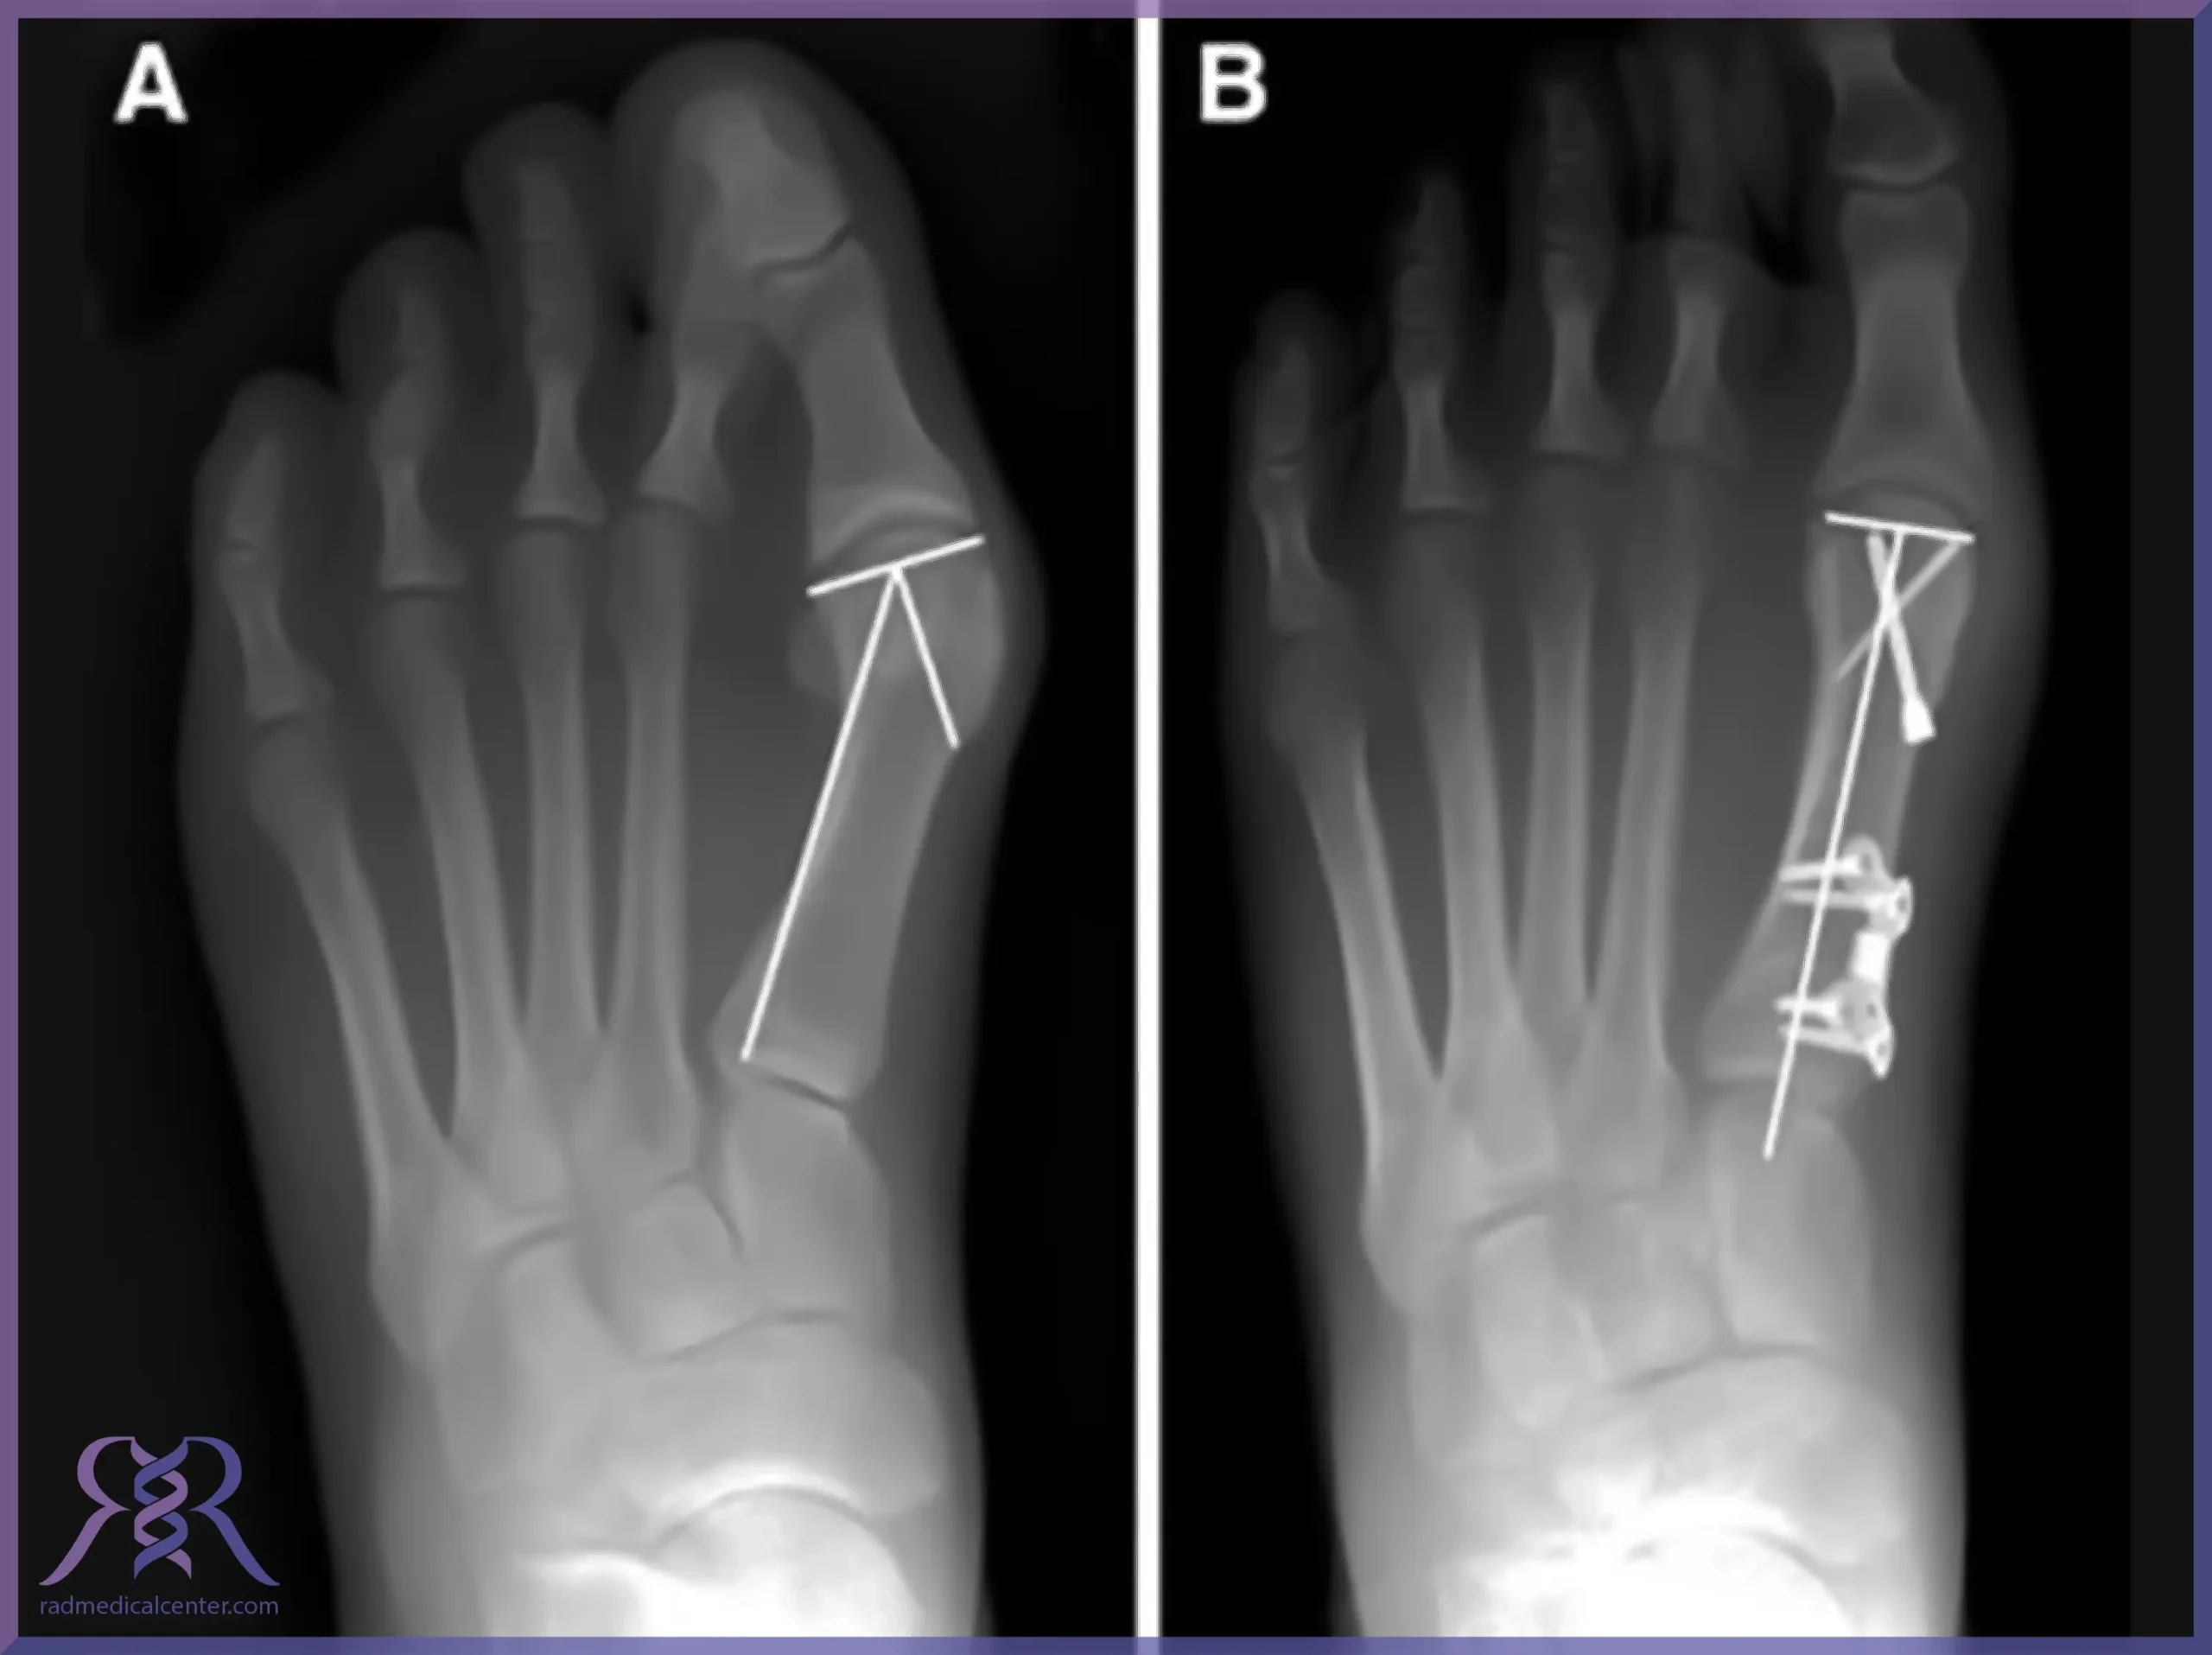

۳. جراحی ارتوپدی:

در این روش انحراف شست پا با استفاده از اندازه‌گیری و تصاویر رادیولوژیک تصحیح می‌شود. این روش به دلیل دقت بالای آن در تصحیح هالوکس والگوس بسیار موثر است.